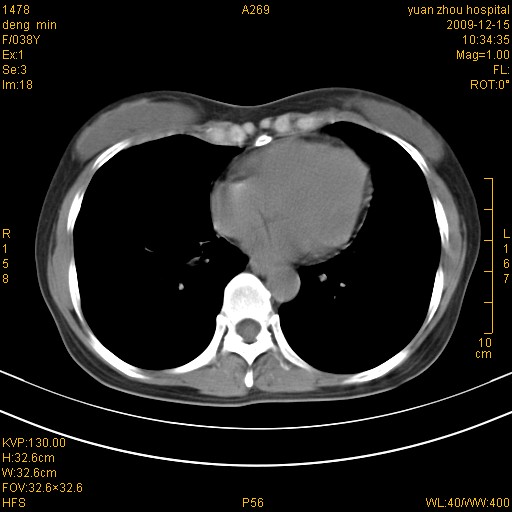

标题: CT23919:F38Y 咳嗽月余 [打印本页]

标题: CT23919:F38Y 咳嗽月余

右肺中下叶、左肺上叶舌段及左肺下叶支气管扩张合并感染。